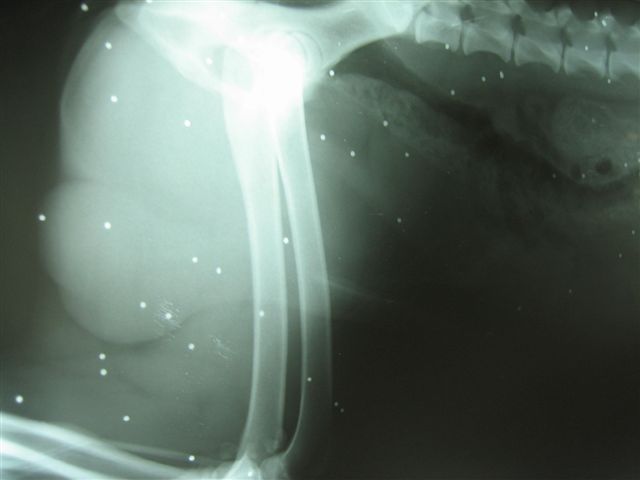

Kod ozljeda od puščanog zrna ili sačme tj kod prostrijelnih rana najbolje je otići do prvog veterinara da se zaustavi eventualno krvarenje i da se utvrdi stupanj ozljede. Ako rane nisu po život opasne tada treba otići do veterinarske ambulante koja ima rtg aparat i poslikati cijelo tijelo da se vidi gdje je završila sačma.

Nije rijetkost da ona bude razasuta po cijelom tijelu što se i vidi iz primjera s rentgenograma . To je jedan ptičar talijanskog lovca koji je propucao svog vlastitog psa u lovu. Nakon terapije koju je pas dobio u našoj ambulanti, pušten je kući i dan danas ide u lov jedino što je sačma ostala u njemu.

Drugi primjer je propucavanje ekstremiteta gdje je došlo do frakture kosti i napravljena je osteosinteza. Pas je danas dobro i trči kao da ništa nije bilo.